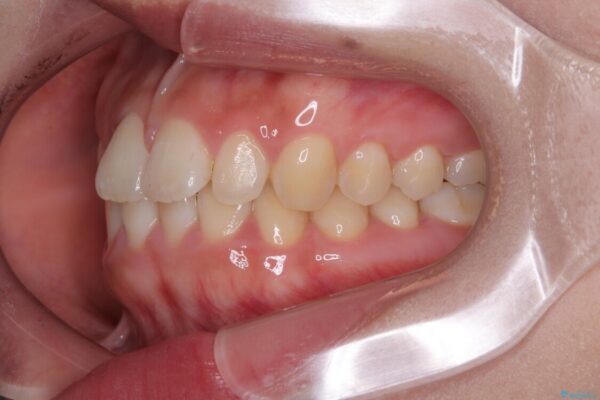

治療途中

• 目立ちにくい表側装置で1年完了!狭いアーチを側方拡大し前歯のデコボコを整えた症例 治療途中画像